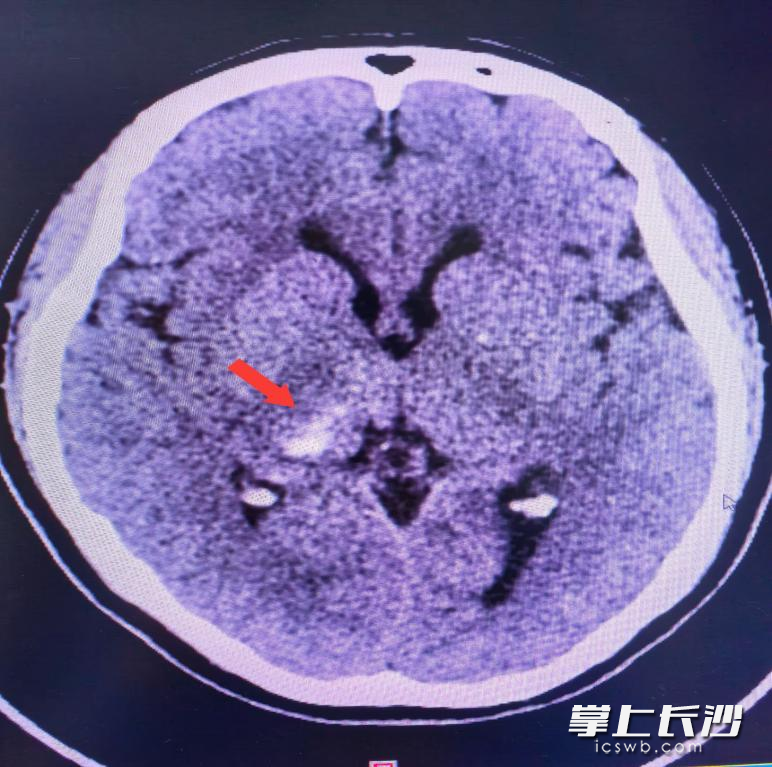

脑梗加上脑萎缩,她差一点就猝死了.

图片尺寸830x685